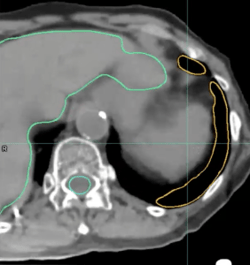

Liver: 2D Brush Tool + Contour CoPilot

In this instance, an adjustment is necessary on separate sections of the liver contour.

liver contour - 3a -contour copilot

To remedy this, the 2D Brush tool is used with Contour CoPilot to make a quick adjustment on a few slices.